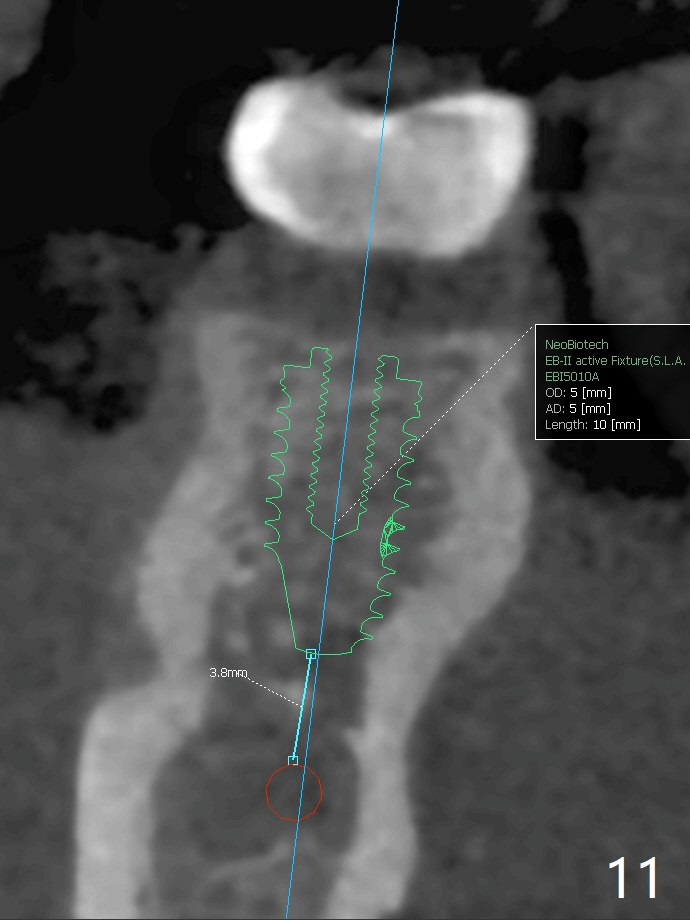

One year 4 months post banding (M) with 16x16 wires, UR3 is being distalized using UR7 as anchor (Fig.1), while the upper dental midline matches the facial one (Fig.2). The anterior overjet remains large (Fig.3). When UR3 is fully distalized, place posted wire to distalize U2-2 together. U2-2 distalization seems to be slow with one 16 mm closed coil spring each side (between 7 and post) 1 year 10 months post banding. Since the upper anterior PA shows mild root resorption at UR2 (Fig.4), a 14 mm closed coil spring is added each side (between 6 and post, Fig.5,6). LR6 has pain 2 years 2 months post banding (Fig.7). Debridement confirms non-salvageability; a 5x11.5 mm implant will be near the mesial root (Fig.8). Power chains for a month leads to closure of the gap between 3 and 4 (Fig.8-11). The space between 4 and 7 is 15 mm. A 12 mm 1st molar crown will be made, while the remaining 3 mm space will be closed by mesialization of 7 using 2 power posts mesial and distal to 6 and 7. Draw 2 tubes of blood. Make an incision to expose the mesial crest of 6.